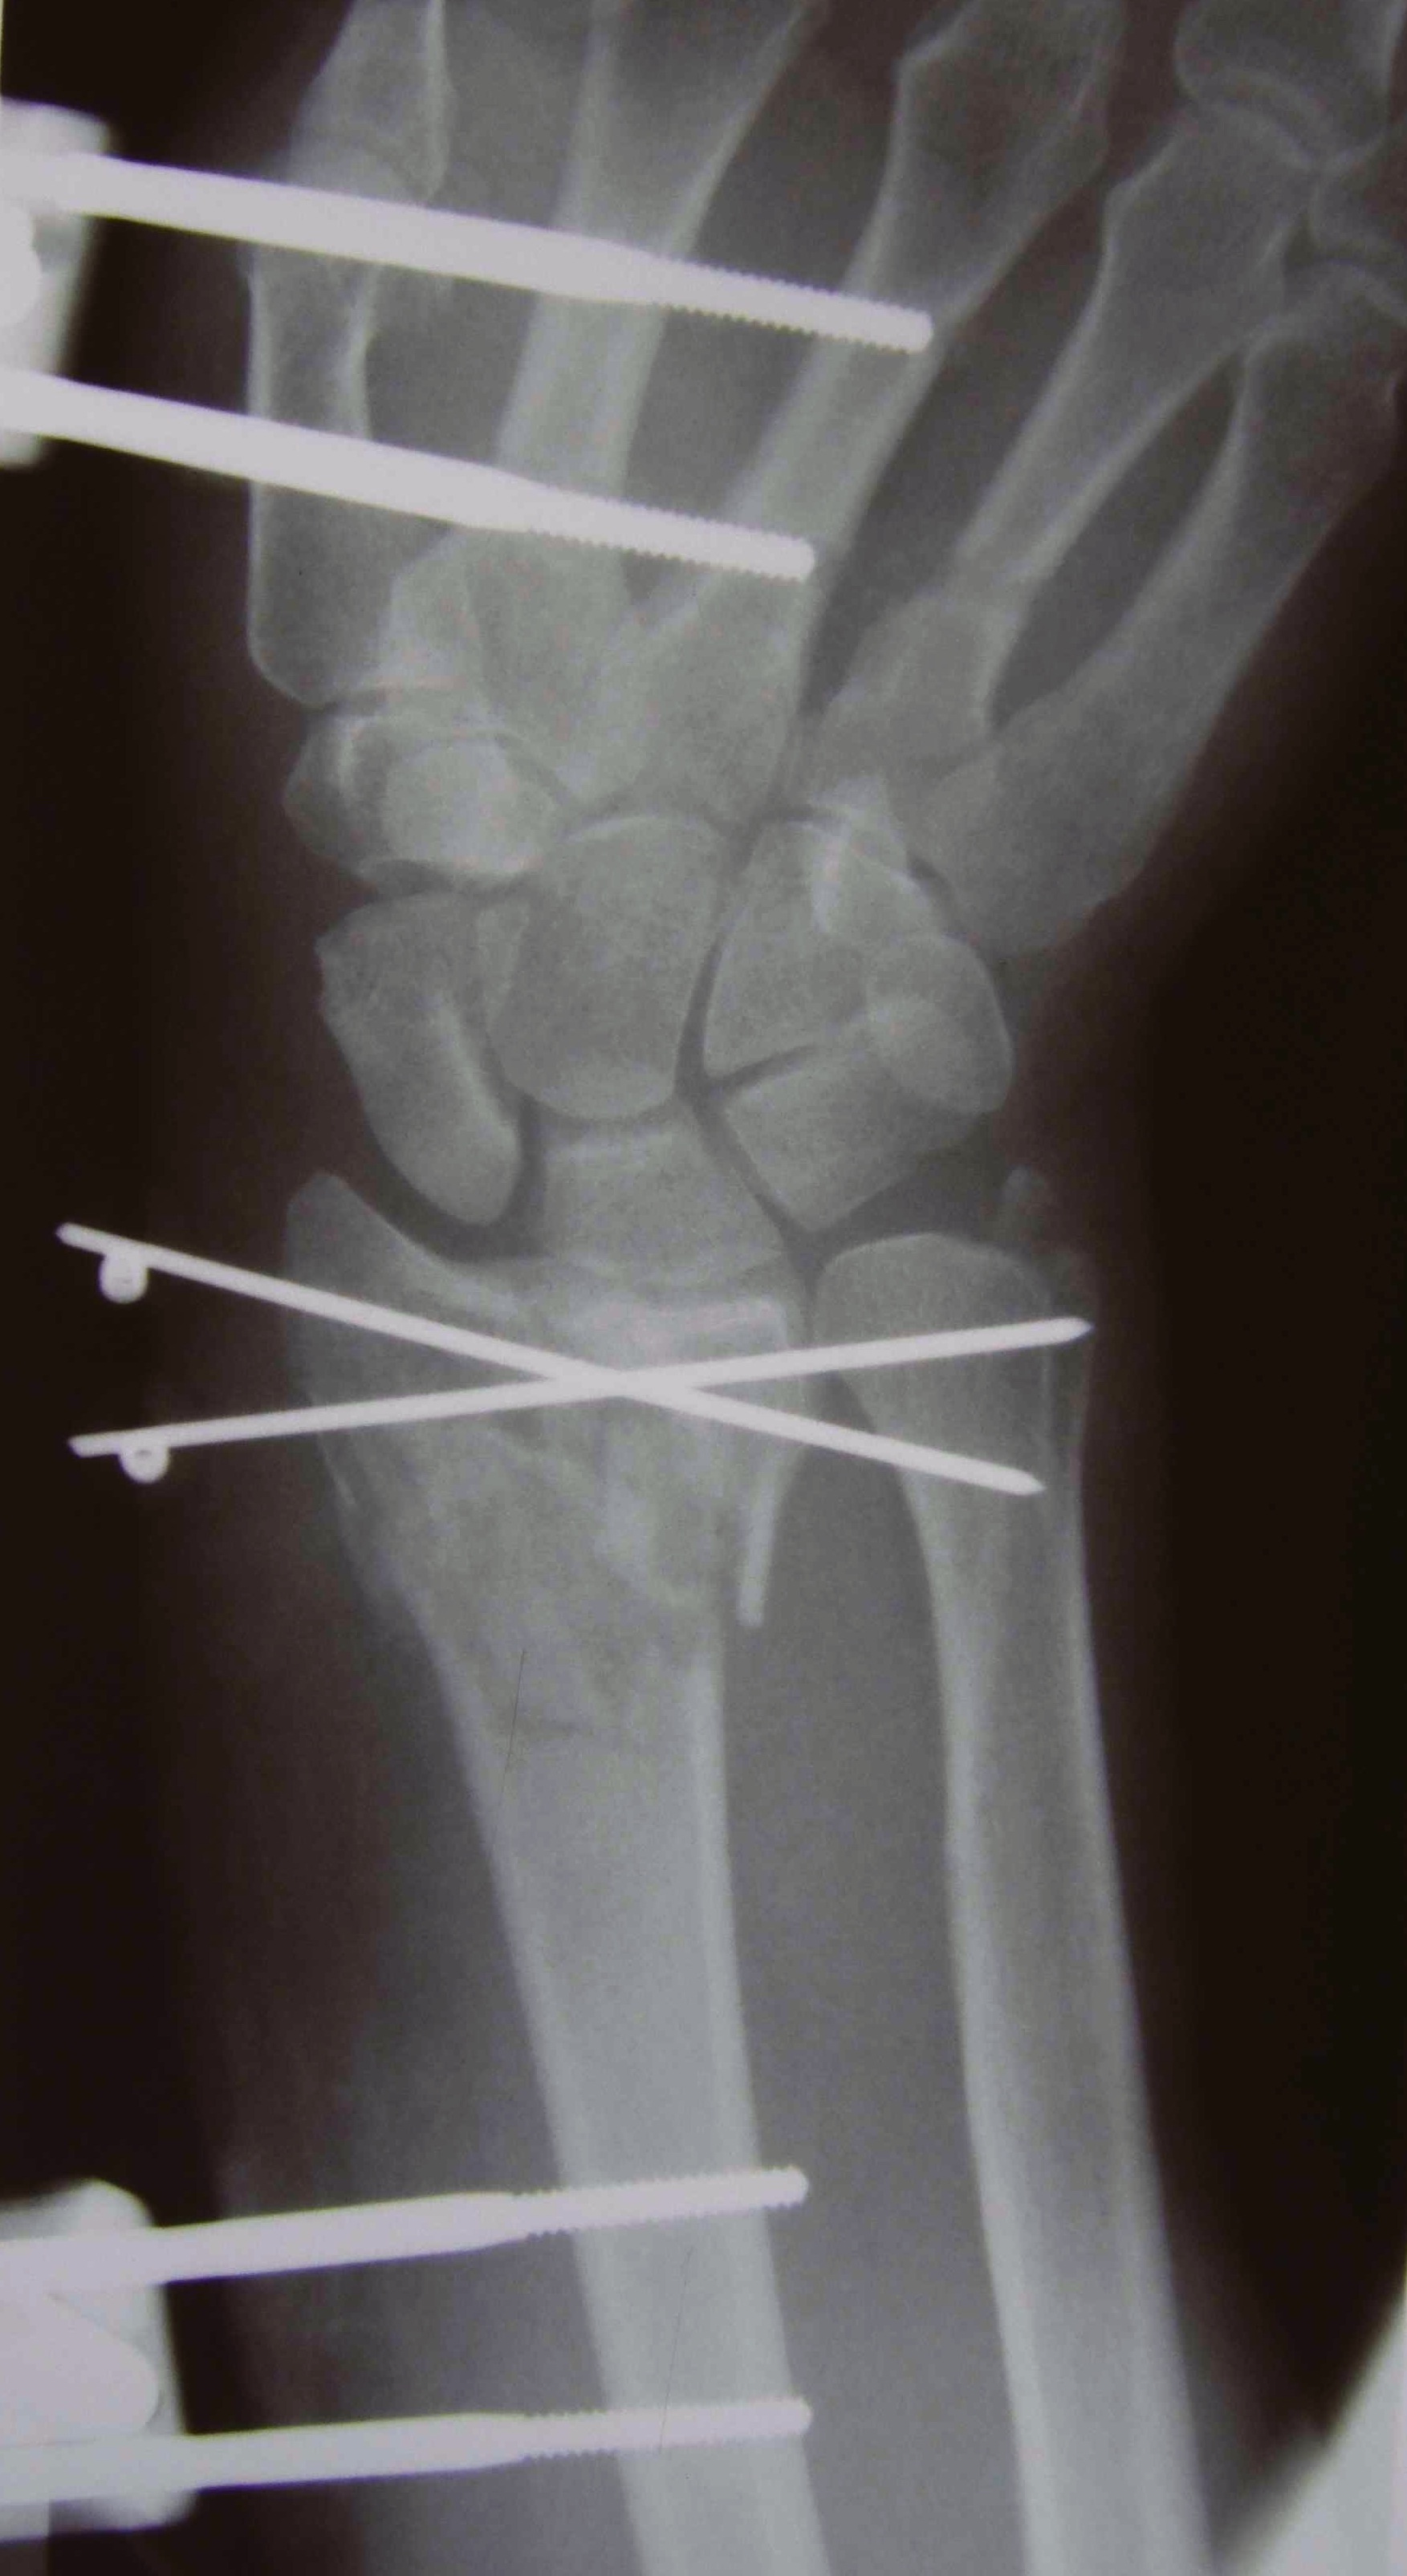

Percutaneous K Wire

Issues

Increased pin site infections

No early immobilization

Technique

Youtube K wire distal radius fracture video

Reduce fracture under anesthesia and fluoroscopy

Radial K wire

- through radial styloid

- can make small incision / blunt dissect to protect branches SRN

- cross fracture site and engage other cortex

- 1.6 or 2 mm K wire

Dorsal K wire Kapandji technique

- percutaneous by hand into fracture site

- tilt distally to reduce dorsal displacement of distal fragment

- drive into proximal radius and engage volar cortex